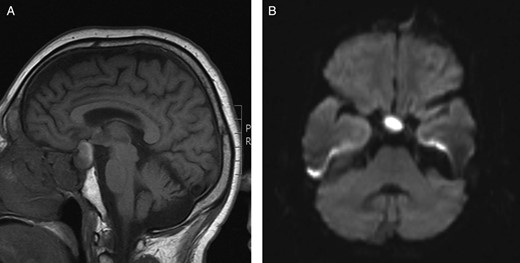

(A) Preoperative sagittal T1-weighted MRI showing a predominantly isointense lesion in the pituitary fossa with some high signal posteriorly. (B) Preoperative axial diffusion-weighted MRI demonstrating a hyperintense lesion in the pituitary fossa.

Endocrine biochemistry was indicative of hypopituitarism [cortisol 90 nmol/l, thyroid-stimulating hormone 1.22 mU/l (T4 6.7 pmol/l), testosterone <0.4 nmol/l]. Magnetic resonance imaging (MRI) revealed a cystic sellar lesion compressing the optic chiasm (Fig. 1). Computed tomography scanning demonstrated an uncalcified hypodense cystic lesion within the sellar. Based on the radiological appearances, a macroadenoma or craniopharyngioma was suspected. A transsphenoidal decompression was undertaken whereupon yellow pus was encountered within a predominantly cystic sellar mass. The atypical appearance of the purulent material prompted sampling for microbiological assessment. The lesion was drained and the remaining cavity was thoroughly irrigated with saline. Histological examination of the lesion revealed columnar epithelial cells characteristic of RCC, some of which were ciliated, resting on connective tissue. Admixed inflammatory cells were also observed including quite numerous neutrophils (Fig. 2). The histological differential diagnosis included abscess, pituitary apoplexy and RCC with superimposed inflammation. While histological examination suggested pituitary apoplexy as an alternative pathology, this was not consistent with the clinical presentation. Although initial gram stain was negative for organisms, the pus retrieved grew Staphylococcus aureus sensitive to flucloxacillin and fusidic acid on microbiological culture. The overall picture was suggestive of abscess formation within a RCC.

Unfortunately, MRI is not specific in identifying pituitary abscess as the signal intensity of an abscess may be affected by its protein content or the presence of haemorrhage. MRI may demonstrate a pituitary abscess as a generally homogenous cystic lesion, typically hyperintense on T2-weighted images and isointense on T1-weighted images, surrounded by a ring of contrast enhancement, although this appearance is variable [6]. Some pituitary abscesses may also show high signal intensity on diffusion-weighted MRI [5]. Other sellar lesions which may exhibit a restriction of diffusion on MRI include macroadenomata, apoplexy and autoimmune hypophysitis. Although restricted diffusion was demonstrated in our case (Fig. 1B), the ambiguous clinical and radiological features focused our preoperative suspicions on commoner pathology (i.e. a macroadenoma). While autoimmune hypophysitis may present clinically and radiologically in a similar fashion, the characteristic histopathological finding of lymphocytic infiltration within pituitary tissue was absent. Although not apparent in our case, secondary pituitary abscesses may share radiological characteristics with the lesions from which they arise [6].